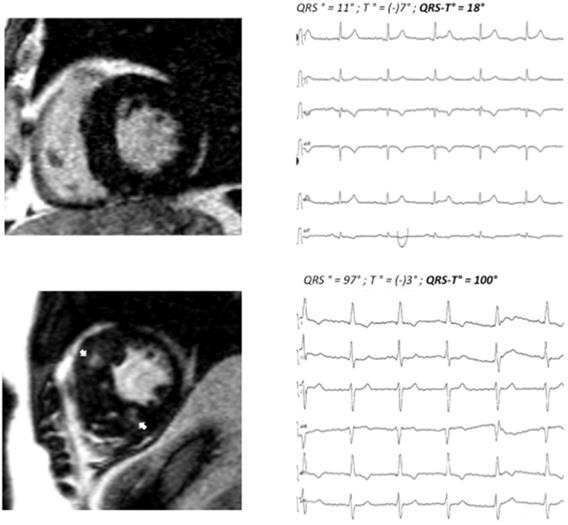

70 consecutive patients (42 male, age 67.7±14.8 years) with HCM were enrolled. Patients were divided into two groups according to the presence (n=43) or absence (n=27) of myocardial fibrosis (LGE) on contrast CMR. Patients with fibrosis had a wider QRS-T angle as compared to patients without fibrosis (100°±54° vs. 46°±31°; <0.001). 24 of 43 patients in the fibrosis group had a QRS-T angle of 90° or more, whereas only 1 of 27 patients in the non-fibrosis group displayed a pathologic QRS-T angle. For clinical examples, also see Figure 1.

Figure 1

Patient A: basal end-diastolic LGE image showing moderate asymmetric LVH (15 mm MWT), no LGE, QRS-T angle 18°. Patient B: corresponding LGE image showing massive septal LVH (26 mm MWT), typical mid-myocardial LGE pattern in the interventricular septum (arrows). MWT maximum wall thickness, LVH left ventricular hypertrophy. LGE late gadolinium enhancement.